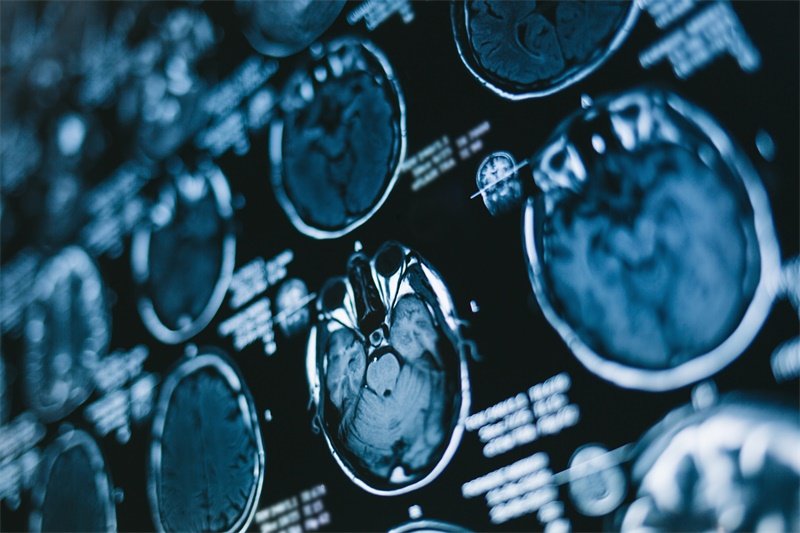

在开始放疗前,医生会通过MRI影像融合技术精确勾画肿瘤靶区,就像绘制一张“敌我识别地图”。对于儿童患者,可能需要使用镇静剂确保定位准确。这个过程需要定制专用头膜,上面有定位标记线,帮助每次治疗时精准对齐。